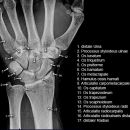

Hand a.p. (dorsovolar)

Beurteilungskriterien

- Kontinuität der drei Karpalbögen (vgl. Handgelenk):

Proximaler Bogen: proximale Gelenkflächenkonturen von Scaphoid, Lunatum und Triquetum

Mittlerer Bogen: distale Gelenkflächenkonturen von Sacphoid, Lunatum und Triquetum

Distaler Bogen: proximale Gelenkflächenkonturen von Capitatum und Hamatum

Fehlende Abgrenzbarkeit, Versatz oder Unterbrechung sind als pathologisch zu bewerten und deuten auf eine Luxation hin.

- M-förmiger Verlauf der Gelenkspalten der Carpometacarpalgelenke? Luxationsstellung in den Carpometacarpalgelenken (meist dorsale Luxation)?

- Gelenkspaltweiten der Carpometacarpalgelenke, der Metacarpophalangealgelenke und Interphalangealgelenke 1 –2mm, der Intercarpalgelenke 1,5 – 2mm

- Täuschungsmöglichkeiten durch Vielzahl akzessorischer Ossikel (abgerundete, zirkulkär-geschlossene Kortikalis), geteilte Handwurzelknochen (Scaphoid, Lunatum, Pisiforme) und Gefäßkanälchen

- Target areas leicht zu übersehender Frakturen:Processus styloideus radii et ulnae, Basen der Metacarpalia (v.a. MCP I) -> großzügige CT-Indikation, Hamulus

Cave: Metacarpale und phalangeale Rotationsfehlstellungen sind konventionell röntgenologisch schwer zu diagnostizieren und zu quantifizieren -> klinischer Befund führend (Fingerstrahl kreuzt bei Beugung im Grundgelenk den benachbarten Strahl), evtl. CT hilfreich.